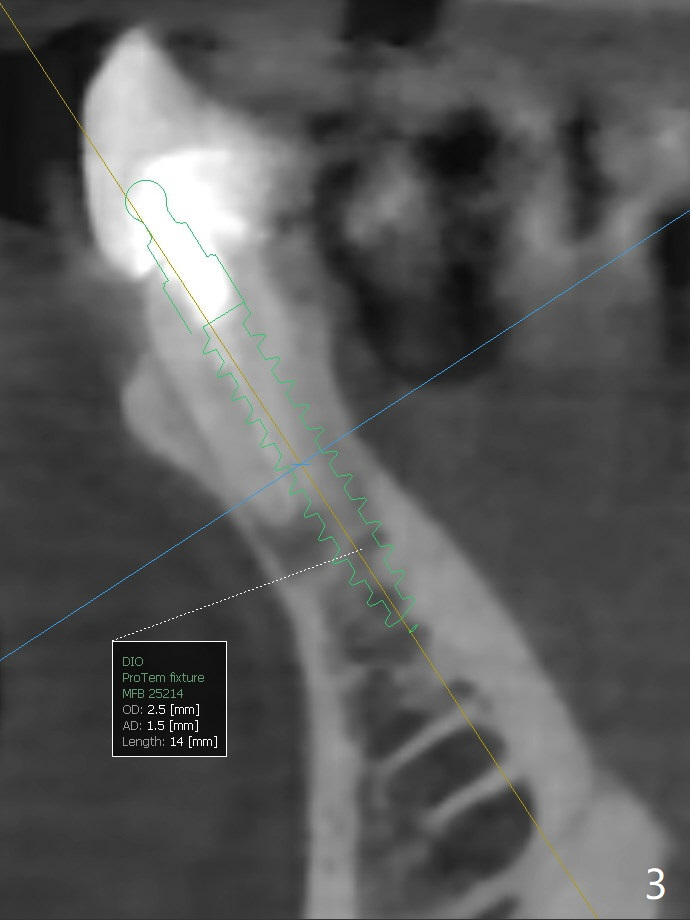

2.5x14(2) mm Implant

A 75-year-old woman with history of full mouth reconstruction requests implant for the tooth #25 with horizontal fracture with PARL (Fig.1-3).